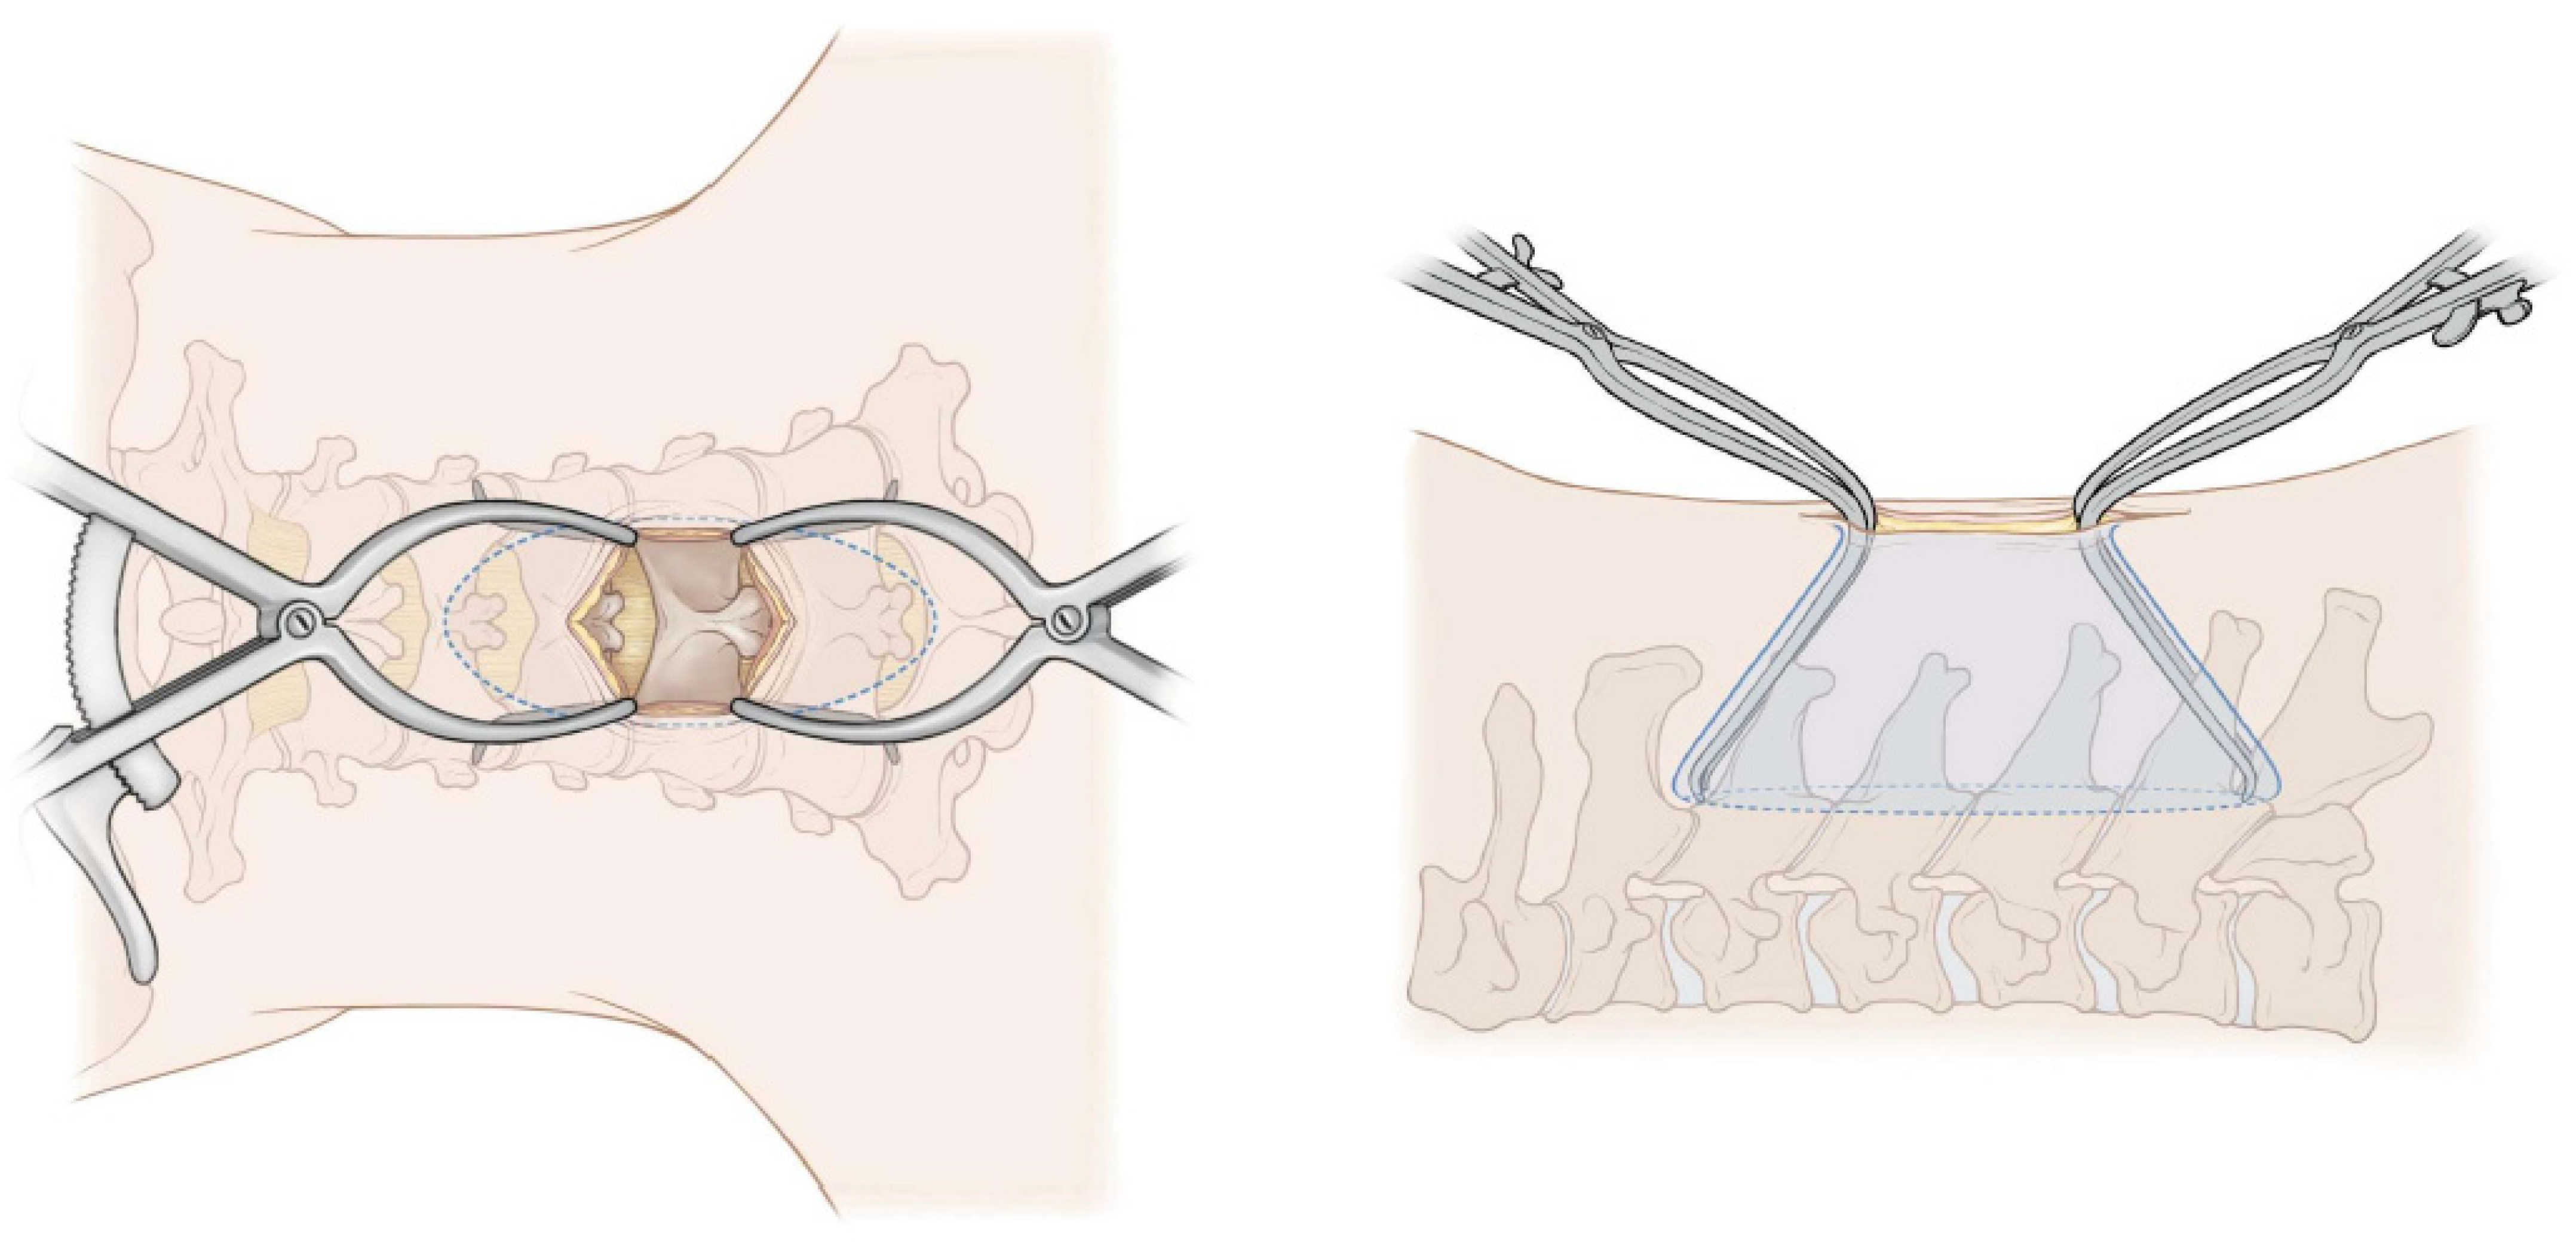

Surgical Technique for exLAP at C3–C6